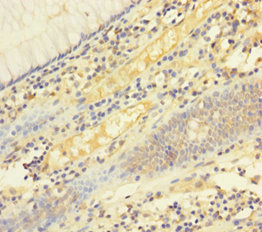

Immunohistochemistry of paraffin-embedded human liver cancer using CSB-PA008434LA01HU at dilution of 1:100